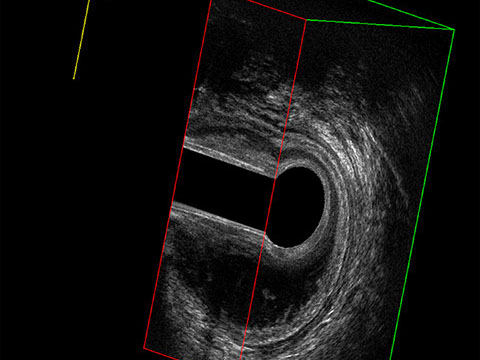

L’ecografia transanale è un esame diagnostico per immagini che consiste nell’introduzione di un trasduttore ad ultrasuoni. Le immagini qualitativamente migliori del canale anale sono ottenute usando un trasduttore rotante, montato in un manipolo rigido, che fornisce un’immagine a 360°. Con le apparecchiature più moderne è anche possibile ottenere immagini tridimensionali.

Proctal dispone di apparecchiatura per ecografia endoanale 3D con sonda rotante.

Sezione Longitudinale 3D con Tramite Fistoloso Intersfinterico Basso Anteriore Semplice